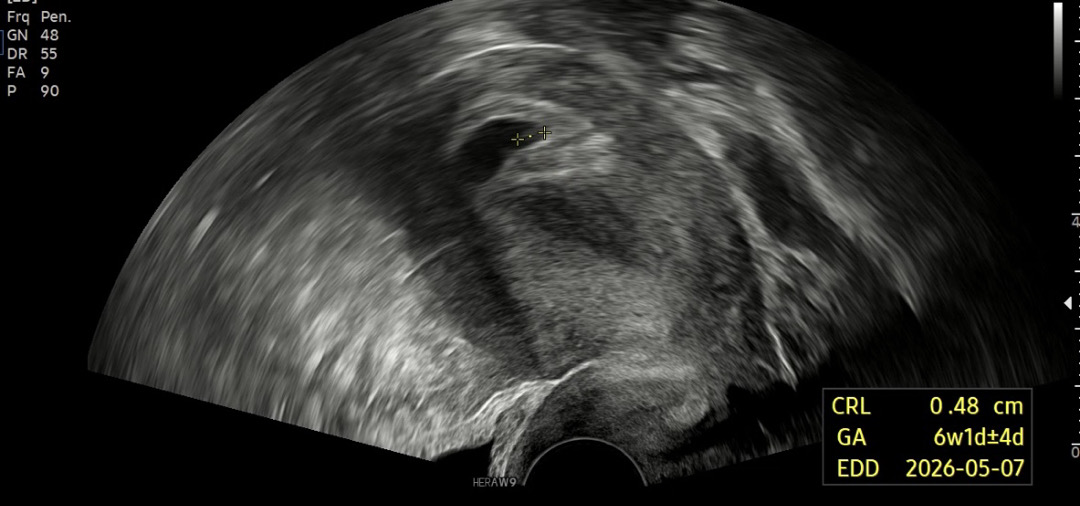

너무 감기거 심해서 예약 한 날짜보다 일찍와서 검사받았는데 코로나확정받았습니다 임신중 코로나 걸리면 태아 슈퍼면역력 생길거라고 웃으면서 초음파 검사했는데 원래로 따지면 8주 입니다 아기집은 크고 아기가 너무 작다고 6주정도로 보인다고 심장소리도 못 듣는다고 의사선생님께서 1주 더 보자고 하시는데 안좋은 쪽이 80프로 확률이라고 하셔서 너무 마음이 아파서 올려봅니다 이러셨던 분들 없으신가요 ㅠㅠ 너무 힘드네요